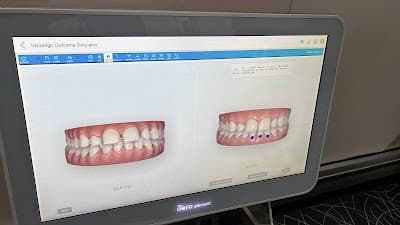

- ✓ Diagnóstico Digital

- ✓ Estética Dental